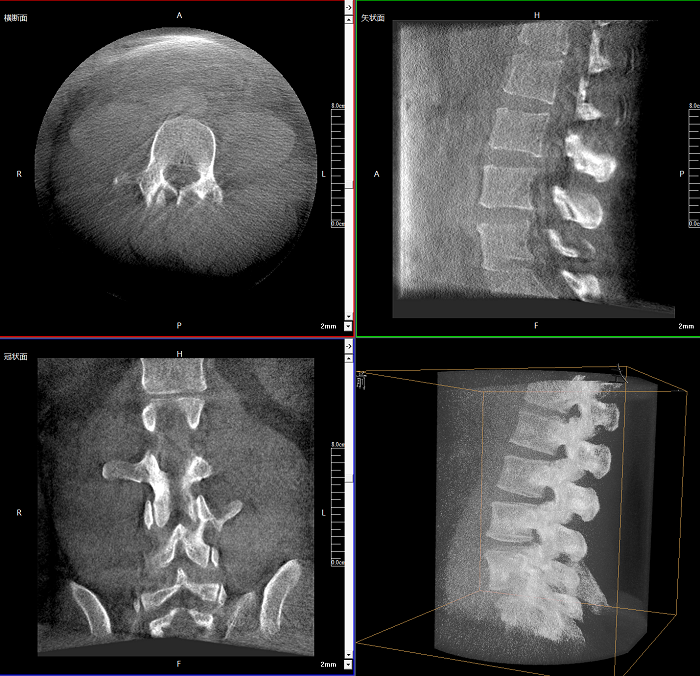

三維成像 全面觀察

任意視角、任意切面觀察

術中實時生成橫斷面、矢狀面、冠狀面及三維影像,可在任意切面、任意角度評估植入物和解剖結構的相對位置。

Clinical picture

臨床圖片